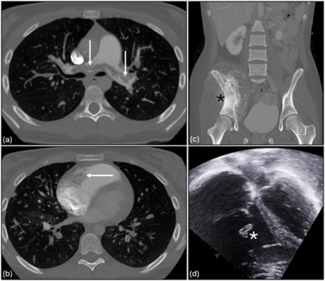

A 72-year-old woman presented with acute onset of abdominal pain accompanied by nausea and vomiting for 10 hours. Computed tomography angiography revealed a ruptured abdominal aortic aneurysm with extensive intraperitoneal hemorrhage.